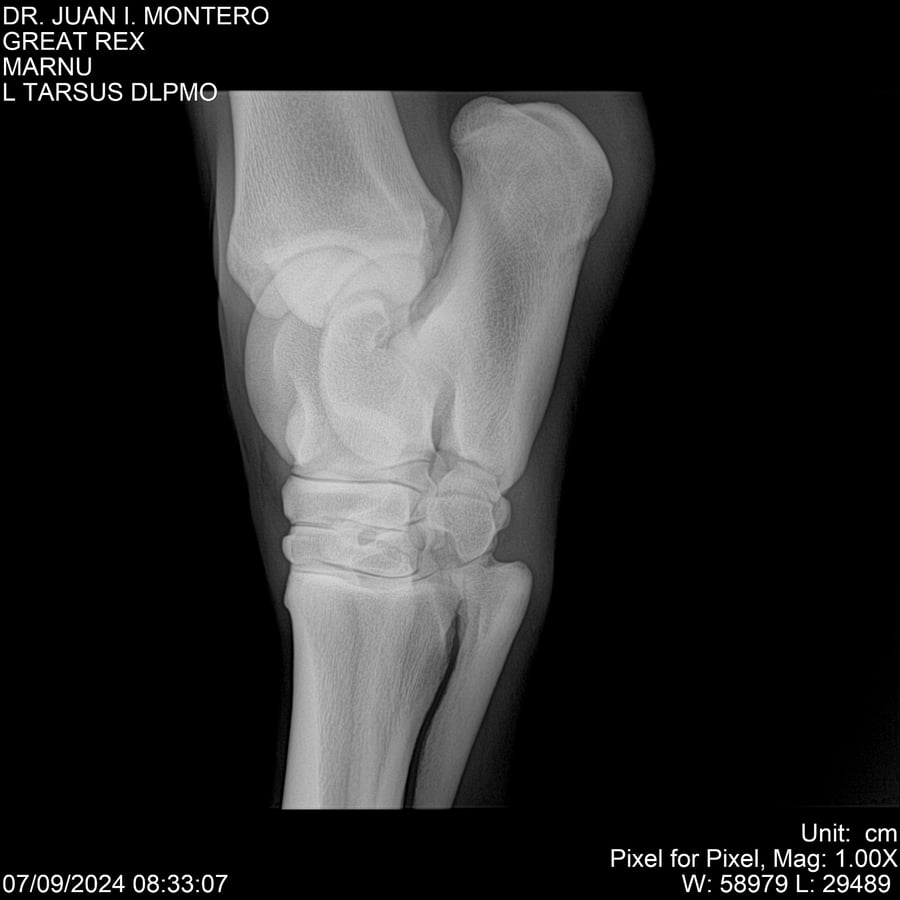

LOTE 4, GREAT REX Lote Anterior Volver al remate Lote Siguiente Ficha Contacto Montevideo - Ficha del Lote Identificador: #282518 Categoría: Yeguarizos Montevideo - 66 Visualizaciones ClicData Contacto Empresa: Abelenda N. R., Walter Hugo Nombre*: Teléfono* : E-mail* : Mensaje Enviar Registrese gratis Este contenido Exclusivo está disponible sólo para usuarios registrados Ingresar